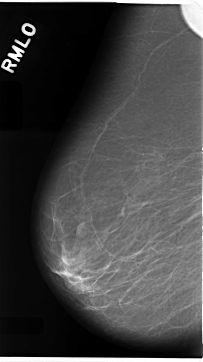

C_0079_1.RIGHT_MLO

RIGHT_MLO LINES 4696 PIXELS_PER_LINE 2632 BITS_PER_PIXEL 12 RESOLUTION 50 NON_OVERLAY